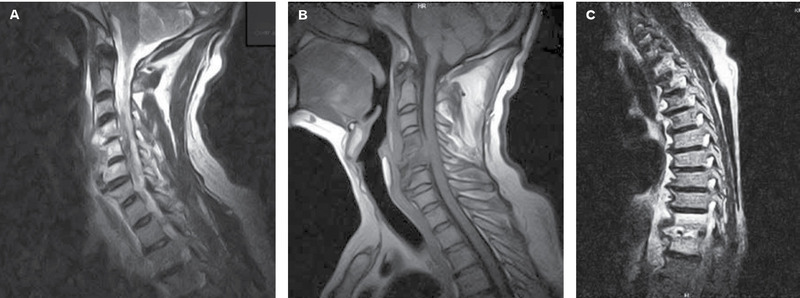

Mężczyzna, l. 54, z wywiadem cukrzycy typu 2, kardiomiopatii rozstrzeniowej i nadciśnienia tętniczego, został przyjęty na oddział zakaźny z powodu zapalenia tkanek przykręgosłupowych. Trzy miesiące wcześniej chory był operowany z powodu ostrego zgorzelinowego zapalenia pęcherzyka żółciowego, powikłanego ropniakiem opłucnej prawej. W wykonanych w tym samym czasie RTG i TK kręgosłupa lędźwiowo-krzyżowego wykazano jedynie zmiany zwyrodnieniowe. Z powodu utrzymujących się dolegliwości bólowych kręgosłupa wykonano badanie MR odcinka szyjnego i piersiowego, które wykazało zmiany o typie spondylodiscitis, obejmujące trzony kręgów i przestrzenie międzykręgowe C4-C5, C5-C6 oraz towarzyszący ropień przykręgosłupowy na wysokości C4-C5 (ryc. 1A, B), a także w odcinku piersiowym zmiany o tym samym typie na wysokości Th11-Th12 (ryc. 1C) z towarzyszącym ropniem przykręgosłupowym. Przy przyjęciu chory skarżył się na osłabienie, silne bóle kręgosłupa odcinka L-S i bóle opasujące w klatce piersiowej, promieniujące do pachwin i wewnętrznej powierzchni ud. W badaniu przedmiotowym temperatura ciała wynosiła 36,8°C, zwracała uwagą bladość powłok, znaczna bolesność palpacyjna wzdłuż szyjnego i piersiowego odcinka kręgosłupa oraz ściszenie szmeru pęcherzykowego po stronie prawej. W badaniu neurologicznym stwierdzono utrudnienie chodu oraz słabo wyrażony objaw Lasegue’a. W badaniach laboratoryjnych stwierdzono niedokrwistość mikrocytarną (RBC 3,82×1012/l, Hg 9,0 g/dl, Hct 28,7%, MCV 75,1 fl, MCH 23,6 pg, MCHC 31,4 g/dl), zwiększone OB (100 mm/h) i CRP (36,8 mg/l), stężenie fibrynogenu wynosiło 825,5 mg/dl, d-dimerów – 1,58 mg/l, a żelaza – 35 µg/dl. Z posiewu krwi uzyskano wzrost Staphylococcus lugdunensis. Zastosowano celowaną antybiotykoterapię. Przetoczono 2 jednostki koncentratu krwinek czerwonych. W wyniku zastosowanego leczenia uzyskano znaczną poprawę stanu klinicznego pacjenta. W stanie ogólnym dobrym chorego wypisano po 19 dniach hospitalizacji. Chory kontynuował leczenie rifampicyną i pefloksacyną w trybie ambulatoryjnym. Ustąpienie zmian potwierdzono w MR odcinka lędźwiowo-krzyżowego wykonanym po ok. 6 miesiącach.